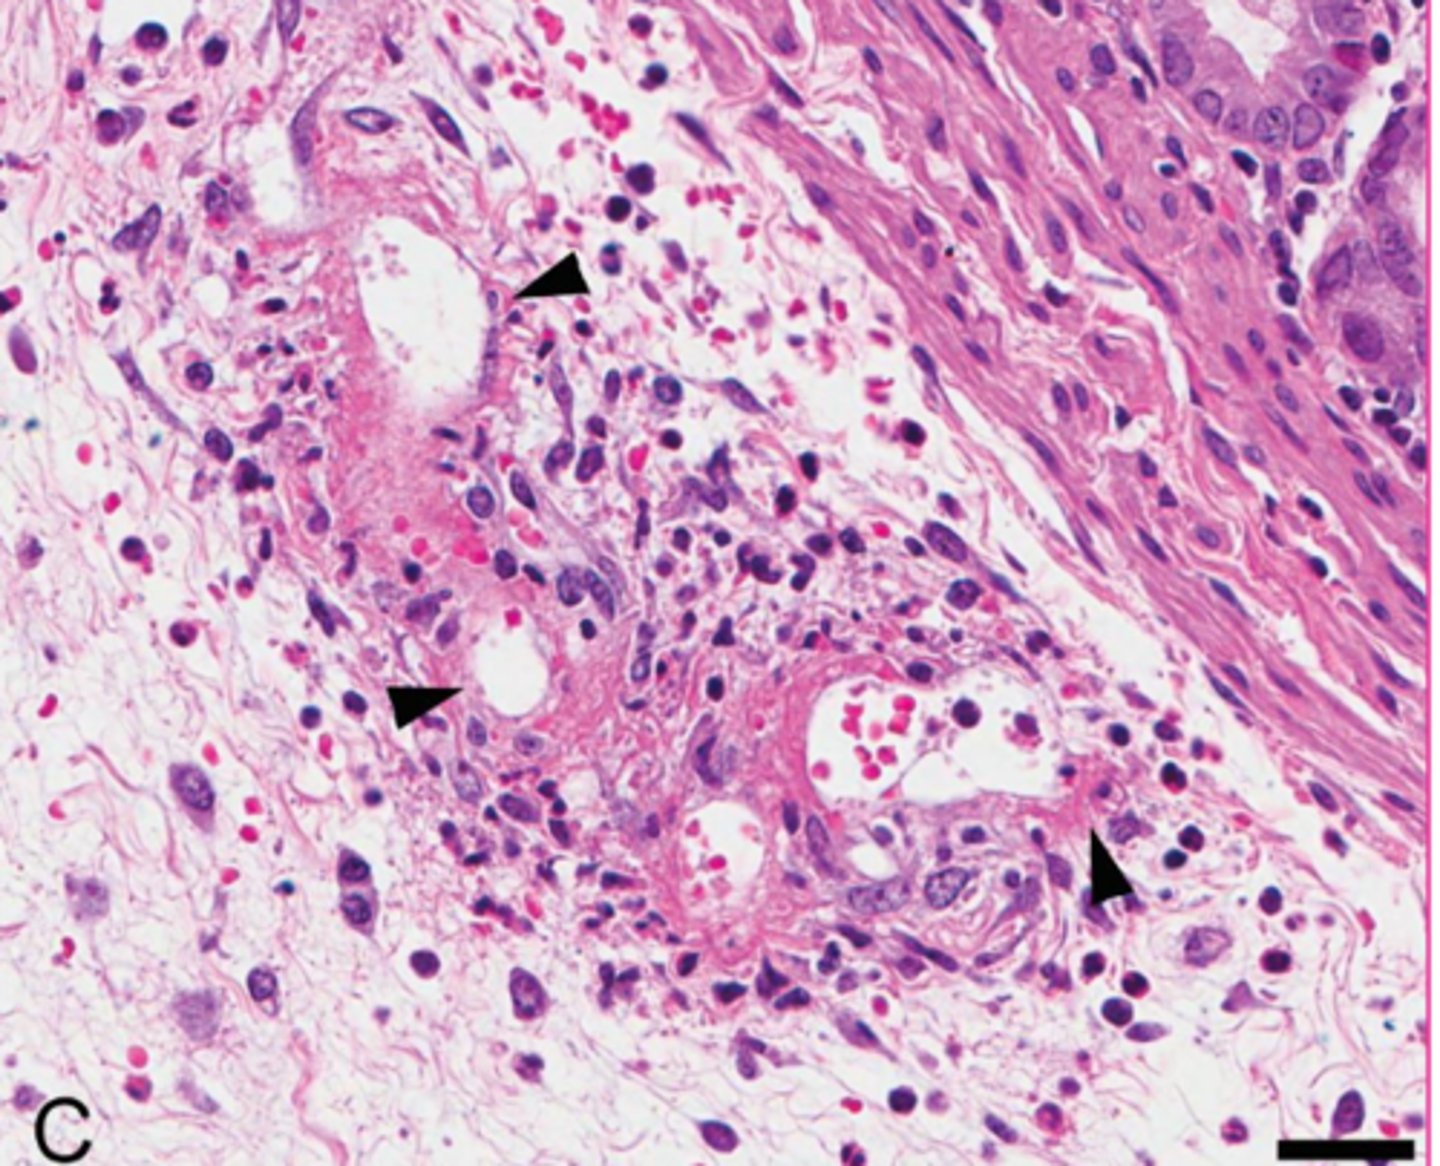

What is the specific term for the inflammatory response ellicited from neutrophils/heterophils and macrophages by gout

50

New cards

renal gout tophi

Describe this extracellular inclusion in the kidney

<p>Describe this extracellular inclusion in the kidney</p>